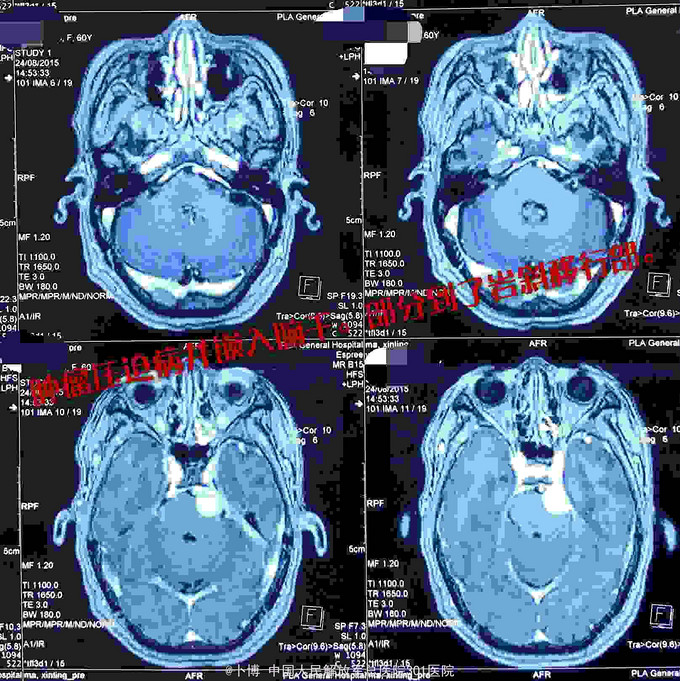

主因左侧面部疼痛3个月入院。有耳鸣。 。

查体:瞳孔等大同圆,光反应敏。眼球各方运动正常,无复视。左侧面部痛温觉下降,无咀嚼肌萎缩。面部对称,眼角口角无偏斜。粗侧双侧听力正常。肌力肌张力正常

诊断:左侧岩斜脑膜瘤。 手术:乙状窦后入路。肿瘤位于面听神经的前方,将三叉神经根推向内侧。为了扩大显露并彻底切除肿瘤(基底),磨除了部分道上结节的骨质。 肿瘤全切。面听神经及三叉神经保留。